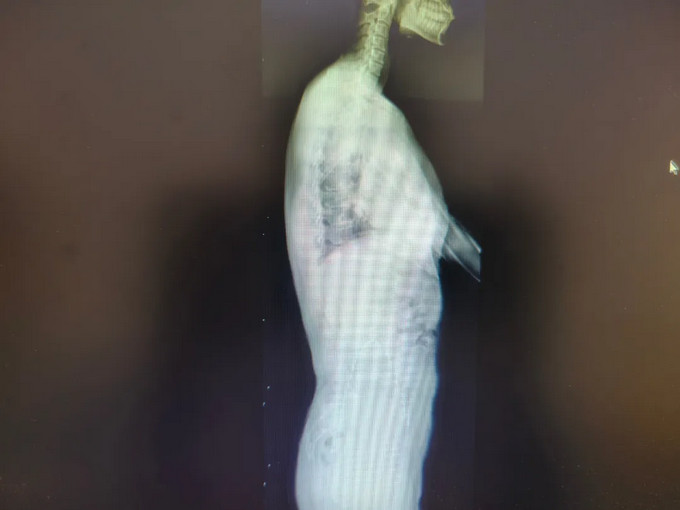

青少年小黃(化名),11歲,家屬發(fā)現(xiàn)脊柱異常1年余。查體:雙下肢真性長度等長,前屈試驗(yàn)陽性,ATR≥5°。全脊柱正側(cè)位片示:“胸椎右側(cè)彎畸形,Cobb角= 23.44 °”。

我院康復(fù)醫(yī)學(xué)科診療團(tuán)隊(duì)診斷:“特發(fā)性脊柱側(cè)彎”,為小黃制定完善的康復(fù)方案:一、脊柱側(cè)彎健康宣教,二、基礎(chǔ)運(yùn)動(dòng)訓(xùn)練(貓卷式、四點(diǎn)撐抗阻脊柱核心訓(xùn)練、側(cè)平板、胸廓打開訓(xùn)練),三、傳統(tǒng)康復(fù)訓(xùn)練(牽伸治療、穩(wěn)定性訓(xùn)練),柱側(cè)彎得到明顯矯正,復(fù)查全脊柱正側(cè)位片示:“胸椎右側(cè)彎畸形,Cobb角= 13.45 °”